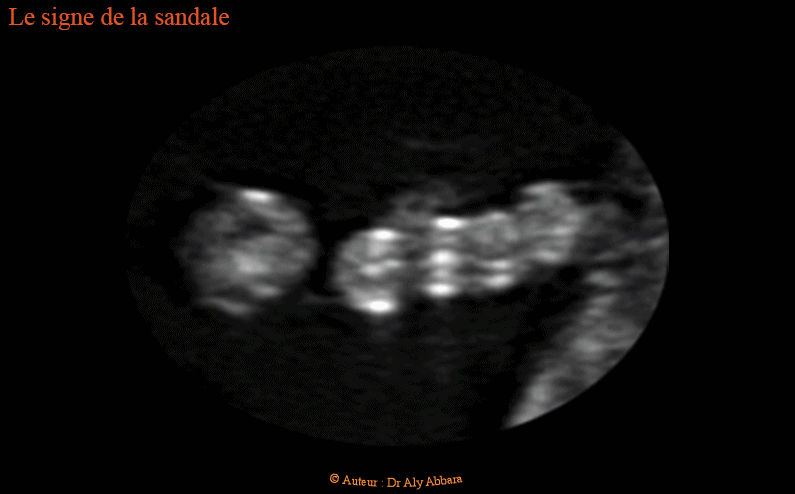

Signe de la sandale chez un nouveau-né trisomique 21 - Il s'agit d'un signe inconstant, plus évident aux mouvements du pied

Images cliniques et échographiques en 2D et en 3D montrant un écartement exagéré entre le grand orteil et le deuxième orteil des pieds (signe de la sandale).

Comme le montre la dernière image, ce signe n'est pas constant : absent quand le pied est en position de repos et plus net quand le même pied est en mouvement. Cette incnostance du signe de la sandale peut être également observée en échographie anténatale.

Le signe de la sandale fait partie des anomalies mineures parfois retrouvées en cas de trisomie 21 (comme c'est la situation, dans les cas présentés dans cet article), mais il peut être observé également chez des foetus normaux.